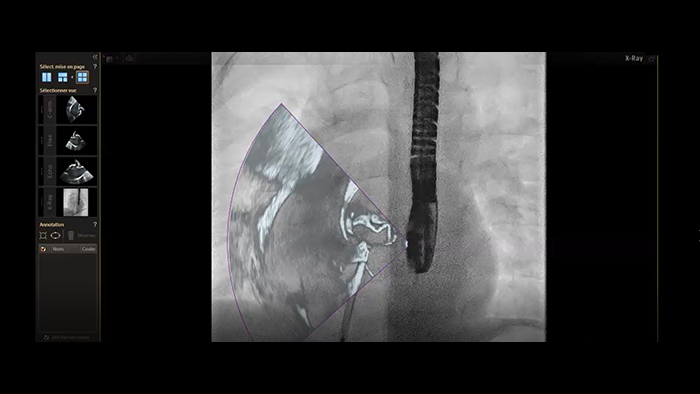

Segmentación del modelo cardiaco de EchoNavigator

Cierre de la comunicación interauricular con fusión en tiempo real de EchoNavigator